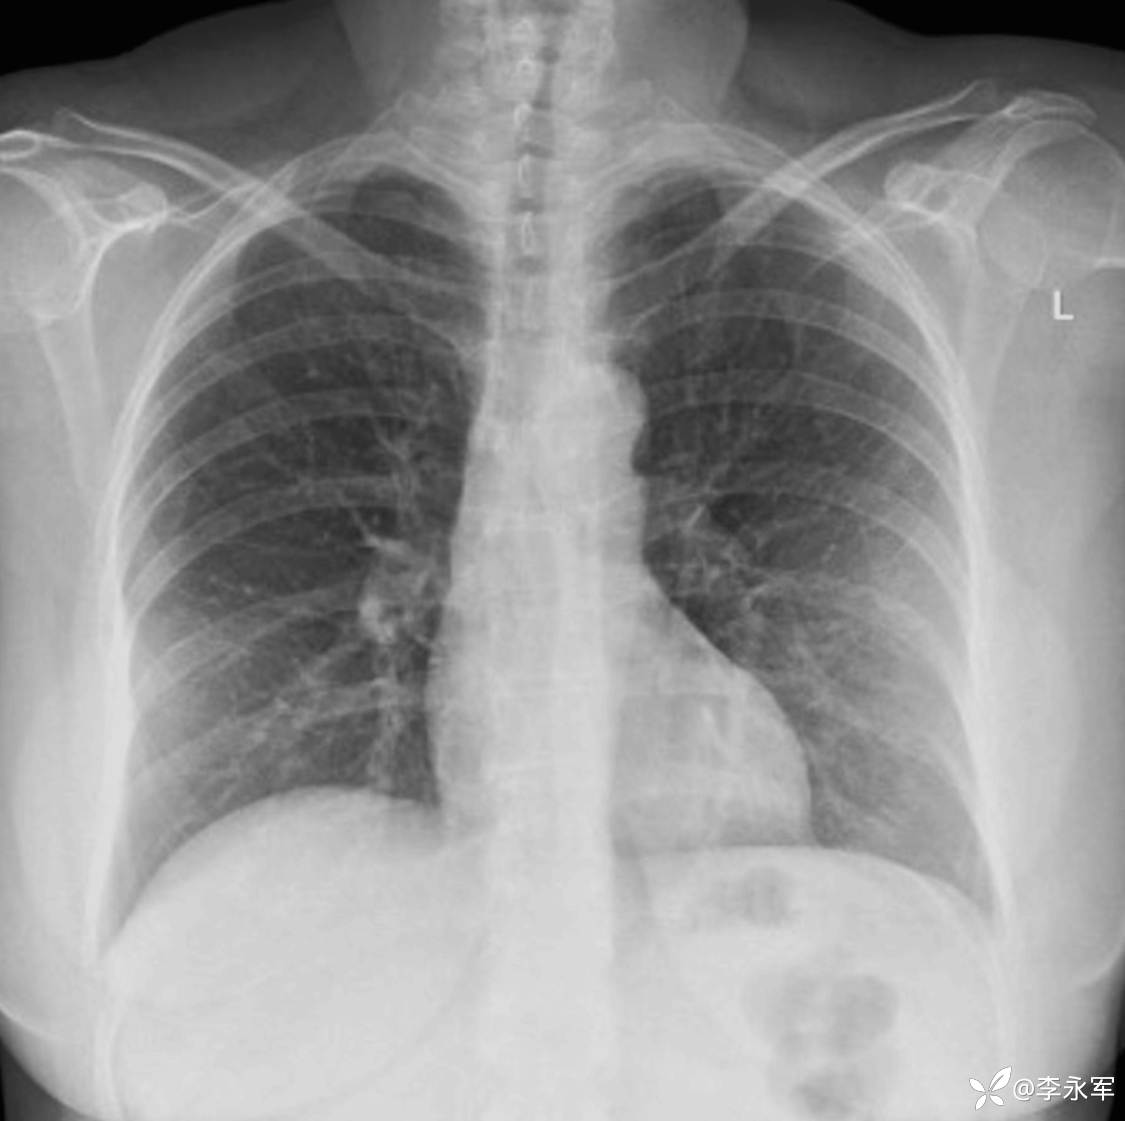

一天前曾因咽喉痛加重和症状持续而至急诊科。当时的胸部 X 光片(图 1)显示支气管纹理增粗,双下肺野周边模糊、边界不清的浸润影,无实变。炎症标志物轻度升高,WBC 8.20 x 10^9/L,CRP 33 mg/L,鼻咽拭子快速抗原检测甲型流感阳性。当时临床状况稳定,生命体征正常,遂予对症治疗和奥司他韦。

图 1:入院前一天的胸部 X 光片